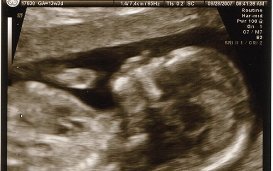

Één van de punten die door het Comité aan de orde zijn gesteld, is de kwestie van de wijdverspreide screening op trisomieën (in het bijzonder trisomie 21, of het syndroom van Down) in de prenatale fase in België, door middel van de NIP-test.

Het feit dat de negatieve perceptie van mensen met een handicap leidt tot een hoog percentage abortussen als gevolg van Downsyndroom, houdt in de praktijk verband met het wijdverbreide gebruik van de NIP-test als screeningsmethode in België. Deze niet-invasieve bloedtest wordt routinematig aangeboden aan zwangere vrouwen en wordt volledig terugbetaald door de Belgische staat. Hoewel zorgverleners verondersteld worden de keuze over te laten aan koppels die geconfronteerd worden met het nieuws van een handicap, worden in België toch meer dan 95% van de zwangerschappen afgebroken in geval van een diagnose van trisomie 21 (zie IEB 25/02/2021).